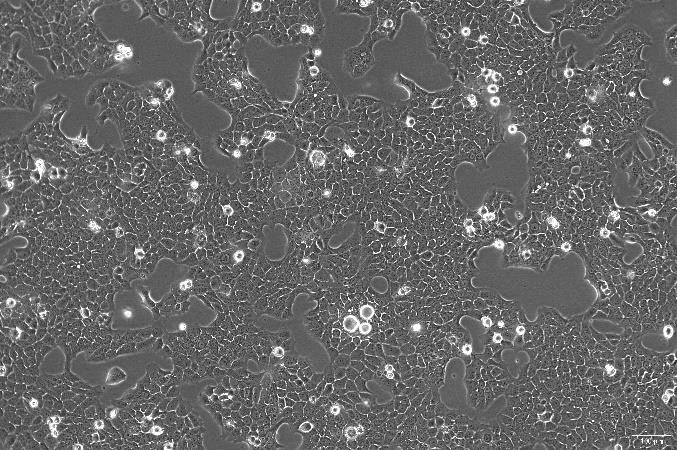

人结肠癌细胞系(SW620)是从一个 51 岁男性白人组织中分离得到的,由 A·Leibovitz 等从一个淋巴结建株。SW620 细胞主要由无绒毛的小园球细胞和双极细胞组成。据报道,SW620 细胞仅合成少量癌胚抗原(CEA),在裸鼠中有高度的致瘤性。

贴壁生长;上皮细胞样 |

品系描述:人结肠癌细胞